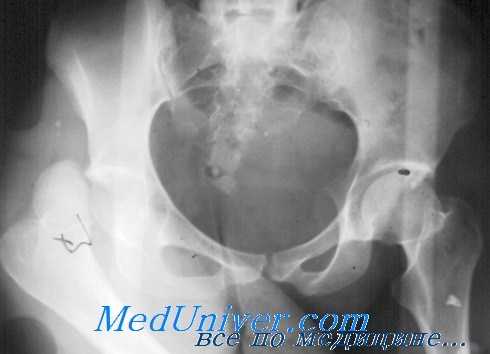

КТ таза. 3D-реконструкция. Красная стрелка – вывихнутая головка бедренной кости, синяя стрелка – «пустая» вертлужная впадина.